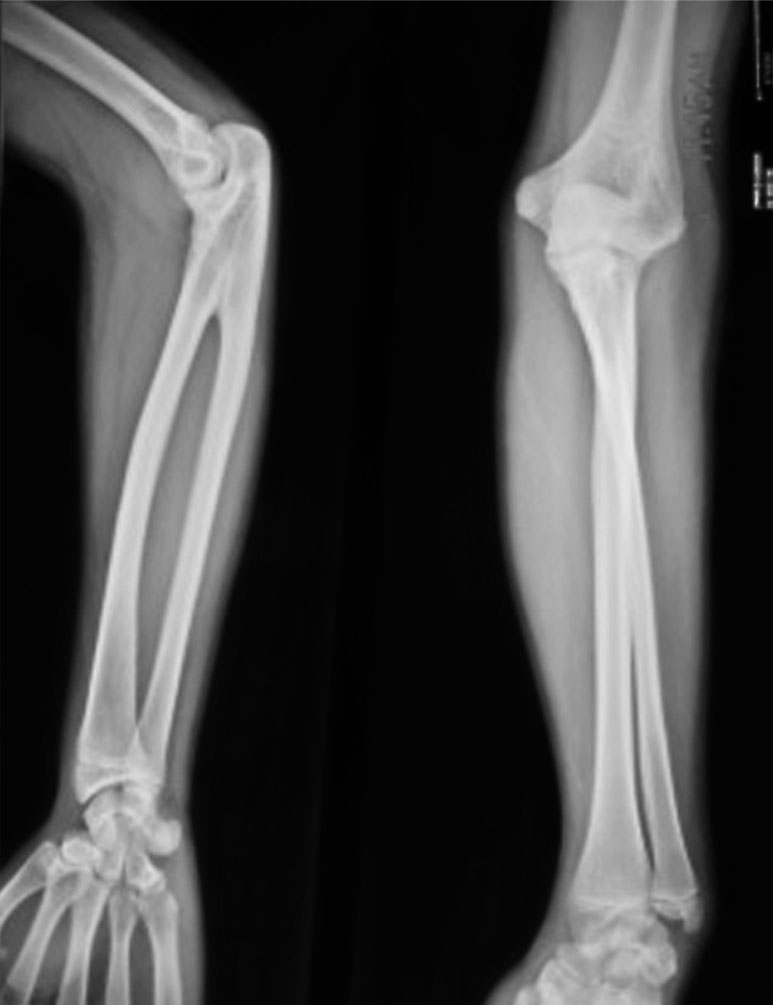

X 线正位片(A)和侧位片(B)显示右侧前臂肱桡骨骨性融合,合并尺骨发育不良

(3)全肘关节骨性融合(图1-2-21)。